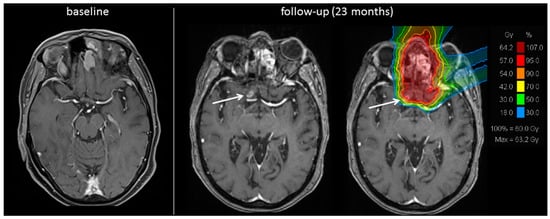

2.2. Group B (Reirradiation, Four Patients)

2.3. Treatment Toxicity